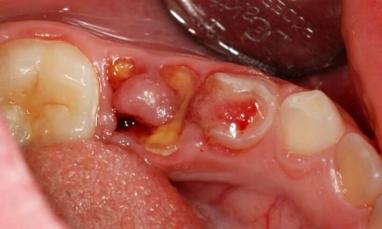

Przewlekłe przerostowe zapalenie miazgi

Typ przerostowy przewlekłego zapalenia miazgi jest niezwykle rzadki (0,5 na 100 przypadków) i charakteryzuje się podziałem na formy ziarniste i polipowate. Polip miazgi zęba (przewlekłe przerostowe zapalenie miazgi) objawia się spuchniętą różową tkanką, która rośnie wewnątrz jamy ustnej. W przypadku formy ziarnistej zębinę zastępuje osteodentyna, a tworzy się również tkanka ziarninowa, która wpływa na próchnicę. W formie polipowatej powstaje polip o wyglądzie grzyba z wrzodziejącą powierzchnią. Przewlekłe przerostowe zapalenie miazgi zdjęcie